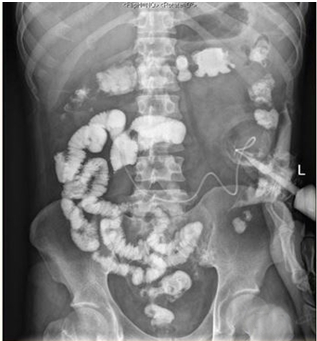

1 资料与方法患者男,30岁,因“腹胀、腹痛6 d,高热1 d”于2017年12月11日由广州南沙区中心医院转诊收入中山大学孙逸仙纪念医院全科医学科。患者本次起病前无明确病因或明显诱因。患者以左上腹轻微胀痛起病,进行性加重。南沙区医院查血常规:白细胞14.27×109/L,血小板50×109/L,中性粒细胞比例74.5%,嗜酸粒细胞1.02×109/L,嗜酸粒细胞比例7.2%。全腹CT+CTA提示:门静脉左右主干及其小分支栓子形成。后在3 d内连续复查血常规,提示血小板进行性下降,由50×109/L相继降至35×109/L、18×109/L;(嗜酸粒细胞计数及比例未能提供),并出现高热(体温39.5℃),因病情危重,遂转诊本院。入院时患者精神疲乏、高热,腹部胀痛难忍,伴有咳嗽。查体:体温38.6℃,心率87次/min,血压102/76 mmHg,指尖血氧饱和度90%~91%。双肺呼吸音粗,双肺均可闻及小水泡音。腹部稍膨隆,叩诊鼓音,左上腹及脐周轻压痛,无反跳痛。听诊肠鸣音减弱,约1~2次/min。当天查血常规示白细胞11.85×109/L,血小板23×109/L,中性粒细胞比例58.1%,嗜酸粒细胞3.5×109/L,嗜酸粒细胞比例29.5%。凝血常规提示:PT 15.9S,PTA 51.1%,PT/R 1.39,Fbg 1.59 g/L,PTINR 1.39,APTT 35.2 s,D-二聚体114.36 mg/L FEU(参考值范围0~0.55 mg/L FEU)。胸部+全腹部CT+CTA示“门静脉主干及左、右支、肠系膜上静脉近端栓子形成;腹主动脉及左侧髂总动脉小附壁血栓;左肺上叶尖后段、左肺上叶下舌段、右肺中叶及双肺下叶炎症;乙状结肠两段节段性管壁增厚,建议排外占位性病变;腹水、盆腔积液,大网膜炎性病变可能性大”。每日复查血常规,发现血小板进行性下降,最低至15×109/L(参考值范围125~350×109/L),嗜酸粒细胞计数及比例进行性升高,分别达到8.07×109/L(参考值范围0.020~0.52×109/L)和51.1%(参考值范围0.4-8.0%)。每日复查凝血常规亦提示凝血指标不断恶化,纤维蛋白原最低降至0.63 g/L。在予禁食、“美平(美罗培南)”抗感染、输注纤维蛋白原及血小板、维护水电解质平衡及营养支持的积极治疗的同时,还积极完善了以下检查寻找病因:①血液系统方面:血浆鱼精蛋白副凝实验:阳性(+);凝血功能实验:PT 15.5S↑,PTA 47.8%↓,PT/R 1.35↑,PTINR 1.36↑,APTT 40.4 s↑,AT-Ⅲ 57.7%↓,F-VII 32.8%↓,F-Ⅷ 68.1%↓,F-X 68.0%↓,F-XII 24.0%↓;纤维蛋白降解产物:381.4 mg/L↑;血栓弹力-血小板图:R时间10.3 min↑;角度18.5度↓;最大血块强度13.2 mm↓;MA(ADP)值5.6 mm↓。骨髓病理学:嗜酸性粒细胞增多(43%),巨核细胞减少(7个)。慢淋/淋巴瘤表型分析:获取和分析细胞数5.0万;粒细胞区百分比82.6%;淋巴细胞区百分比9.4%;单核细胞区百分比2.0%;CD45dim细胞区百分比1.3%;有核红及细胞碎片区域百分比4.6%。ETV6/PDGFRB融合基因、FIP1L1/PDGFRA融合基因(—)。骨髓细胞学病理结果:符合嗜酸细胞增多症;②消化系统检查:大便细菌培养鉴定及药敏提示无志贺、沙门菌生长,有真菌生长;大便难辨梭菌毒素检测(—);粪便找寄生虫、找阿米巴、寄生虫七项均为(—);消化肿瘤系列提示CA-125 244.8 U/mL↑;腹腔穿刺术穿出“血性腹水”,腹水CA-125 1006.0 U/mL↑,腹水找癌细胞(—);复查腹部CT+CTA:乙状结肠两段节段性管壁增厚,建议进一步检查;排外占位性病变;遂行PET-CT:提示全身未见明确恶性征象。行电子结肠镜示:内镜诊断:(1)回肠末段炎症;(2)乙状结肠炎症;(3)内痔。钳取组织送病理,提示:标本①(回肠末端)黏膜组织呈慢性炎,伴糜烂,一些嗜酸性粒细胞浸润(约35个/HPF);②(乙状结肠)黏膜组织呈慢性炎,伴糜烂,个别嗜酸性粒细胞浸润(约4个/HPF)。③风湿免疫系统方面:免疫八项、风湿四项:C反应蛋134.0 mg/L,余未见异常;总IgE 170 IU/mL↑;抗ENA抗体、狼疮两项、血管炎两项、免疫球蛋白G4、抗心磷脂抗体三项均为阴性;④其他感染病原学检查:乙肝、肝炎系列、性病三项、痰找抗酸杆菌、T-spot实验、流行性出血热、登革热抗体、登革热病毒NS1抗原、外斐氏试验、肥达氏试验、痰结核培养、骨髓培养、血液细菌、血液厌氧菌培养均为阴性。经过上述检查,初步考虑“特发性嗜酸性细胞增多症”,于12.15开始予“甲泼尼松龙40 mg静滴, 1次/d”及“低分子肝素0.6 ml皮下注射, 1次/d”抗炎抗凝治疗。患者病情及检验指标有所好转,热退、腹胀减轻,血常规提示血小板升至49 ×109/L,嗜酸粒细胞计数和比例均下降至正常,凝血常规提示D-二聚体降至47.90 mg/L FEU。但12-22患者自行进食多量米饭后突发腹胀痛较前加重,急查血常规提示白细胞升至21×109/L,血小板再次下降至15×109/L,D-二聚体升至97.28 mg/L FEU,全腹CTA提示“门静脉主干及左、右支、肠系膜上静脉近端新发栓子形成”,遂于当日转至ICU予“尿激酶20万U+肝素钠1250 U”溶栓治疗后予“低分子肝素0.6 ml皮下注射, 1次/12 h”序贯抗凝治疗。后患者病情渐渐稳定,至2018-1-18患者在“甲泼尼松龙12 mg口服, 1次/d”及“立伐沙班20 mg口服, 1次/d”的维持治疗下,血小板、嗜酸粒细胞计数及纤维蛋白原均回复正常,D-二聚体下降至3.52 mg/L FEU。但遗憾的是,此时患者再次进食大量米饭,约1 h后突发腹痛、气促,急行胸片+腹平片提示:“双侧膈下游离气体,考虑胃肠道穿孔可能;双下肺少许炎症,少量胸腔积液;腹部多量积气伴肠腔扩张”。遂即送手术室行全麻下“腹腔镜探查+坏死空肠切除+大网膜切除+肠系膜上动脉探查+空回肠双腔造口术”,术后病理提示标本①(大网膜)脂肪组织,部分坏死,合并慢性炎,伴一些中性粒细胞浸润,较多泡沫样组织增生,未见明确血栓,未见恶性改变。②(部分空肠)肠壁组织,部分肠壁全层坏死,合并慢性炎,肉芽组织增生,未见明确血栓,未见恶性改变。免疫组织化学:CD38浆细胞(+)、IgG(+)、IgG4(﹣)。术后继续予“立伐沙班10 mg/d”和“甲泼尼松龙8 mg/d”口服治疗,并于2018.2.4停用“甲泼尼松龙”。2.28复查全腹CTA,仍可见“脾静脉新发血栓,门静脉及肠系膜上静脉血栓较前好转”。3.20行空回肠双腔造瘘管泛影葡胺造影术提示“双腔造瘘管通畅,右中下腹小肠蠕动尚可,结肠各段及直肠通畅,未见对比剂外漏征象”。但患者合并了严重的短肠综合征,致严重低钾低钠血症和继发的代谢性脑病,病情再度转危。继续纠正电解质紊乱、补充营养,最终病情好转后于4.11行“造瘘口回纳修补术”。随访半年,患者仍口服“立伐沙班10 mg/d”抗凝治疗,复查血常规、凝血常规等各项指标均正常,但营养状况较差。

| 图 1 全腹CTA(2017-12-22):门静脉及肠系膜上静脉血栓形成 |